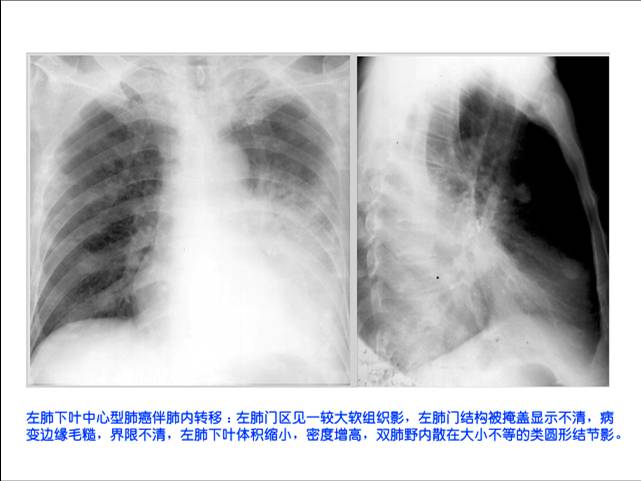

照片名称:作废夏夜中心型肺癌内转移